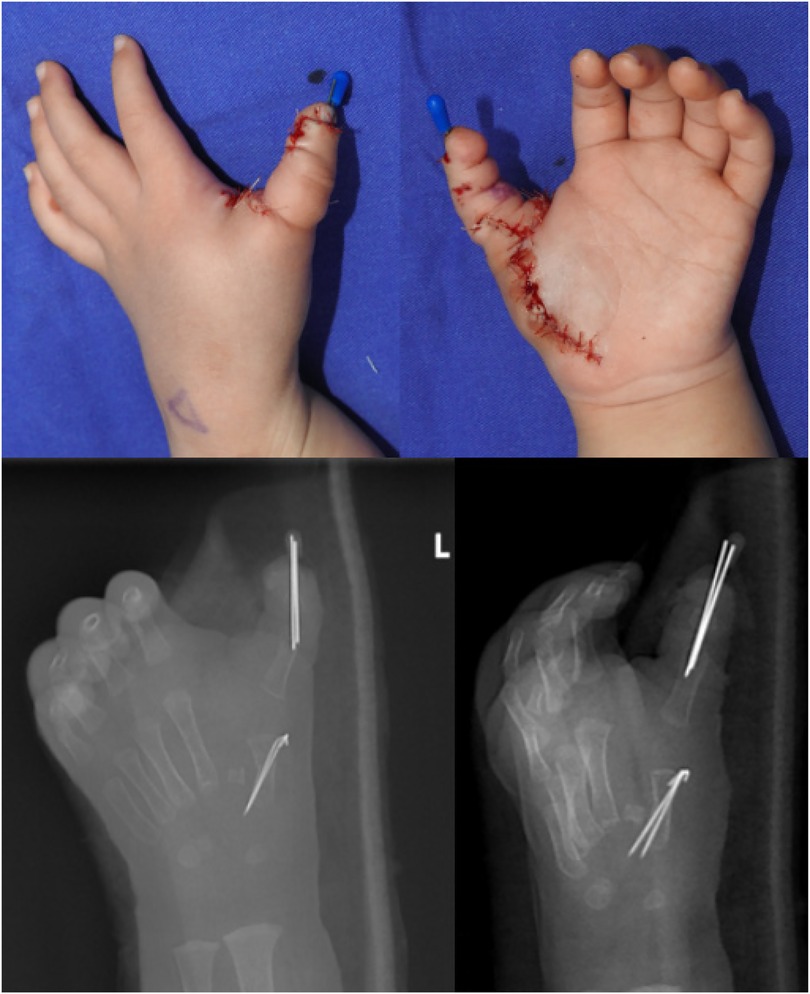

Abstract Congenital anomalies of the hand and forearm present a complex challenge in plastic and pediatric surgery. We present the case of a 13-month-old child with a congenital left mirror deformity, characterized by the presence of eight digits and two ulnae exhibiting near-perfect bilateral symmetry. A novel palmar-based incision design was employed for the corrective and functional reconstruction of the left hand,which may serve as a reference for the surgical management of similar conditions. Preoperatively, the radial-side middle finger demonstrated palmar opposition against the ulnar aspect of the palm.The surgical procedure included resection of the radial-sided index, ring, and little fingers , along with pollicization of the middle finger. Functional reconstruction of the neothumb involved restoring adduction and abduction using preserved native anatomical structures. Following comprehensive clinical and imaging evaluations, the patient underwent successful surgical treatment.Postoperatively, substantial improvements were observed in both hand morphology and grasping function. Through our novel palmar incision approach, we effectively reconstructed thumb opposition and adduction while preserving intrinsic hand musculature and achieving optimal scar concealment. In managing mirror hand deformities, meticulous selection of the most dominant digit for thumb reconstruction remains crucial. At the initial surgical stage, osteotomy of the selected digit was performed to enhance its morphological similarity to a normal thumb.